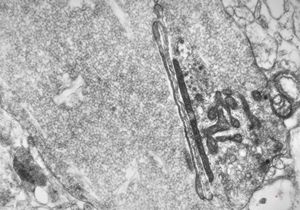

F,50y. | progressive multifocal leukoencephalopathy- viral particles in a glial cell